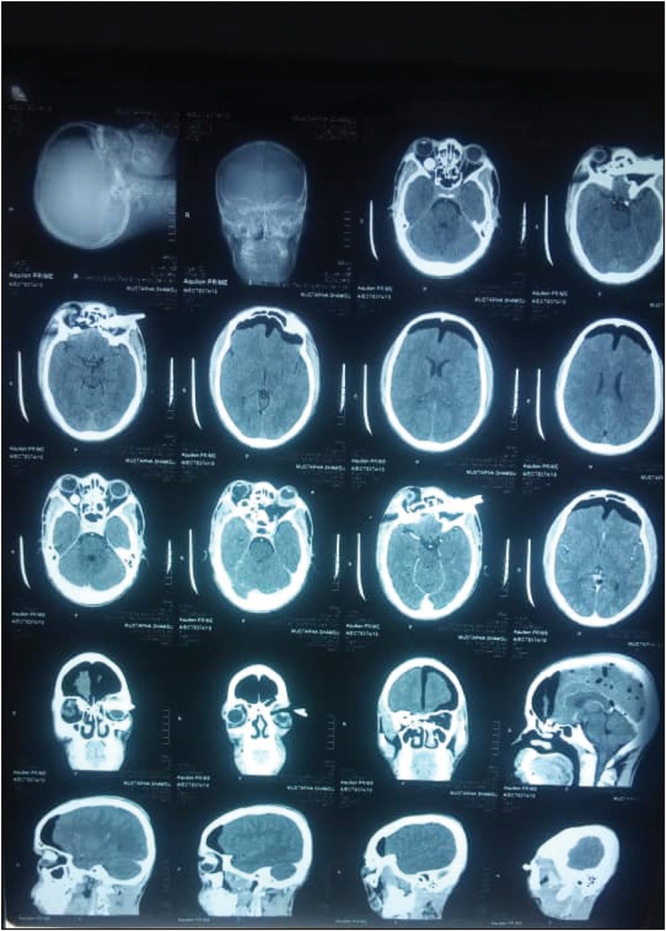

Case report: Intra-orbital FBs are rare, with few cases reported in the literature. This is because the orbit protects the globe from external forces, and the orbit is a closed cavity with one opening. This report details the case of a 28-year-old man who presented to the emergency unit with an 11-hour history of an intra-orbital FB. The patient was lying on a bench when a stationary motorcycle fell on him. He noticed that he was unable to open both eyes and was rushed to a peripheral hospital, then subsequently referred to this tertiary center. On examination, he was ill-looking and anxious but not febrile or pale. Systemic examination did not reveal any abnormality. Unaided visual acuity in the right eye (OD) was nil perception of light, while left eye visual acuity (OS) was counting fingers. The right eyelid was ptotic due to edema. He underwent basic laboratory investigations that were all normal. A plain X-ray revealed a radio-opaque FB penetrating the left orbit, fracturing the medial walls into the right orbit, with the round end positioned behind the right globe. The FB was identified as a broken part of a brake/clutch lever from the motorcycle. A computerized tomography scan showed a metallic object in both orbits, accompanied by pneumocephalus, and suggested transection of the right optic nerve. The patient was prepared for FB removal and repair of the lid penetration under general anesthesia, following review by the ENT surgeon and neurosurgeon. The brake lever was successfully removed, and the patient was administered antibiotics. Post-operatively, visual acuity in the right eye remained at nil perception of light, while that in the left eye improved to 6/9 upon discharge.